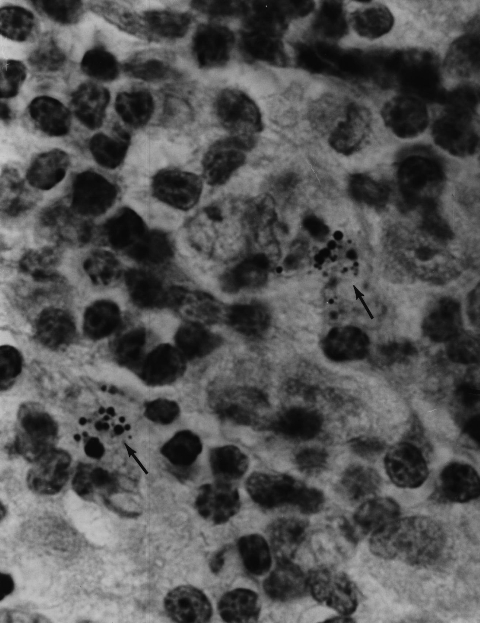

Figure 1. Hodgkin’s (B cell) lymphoma of the lung. Arrows point to a rare collection of intracellular variably staining coccoid forms. MacCallum-Goodpasture Gram stain, magnification x1000, in oil.